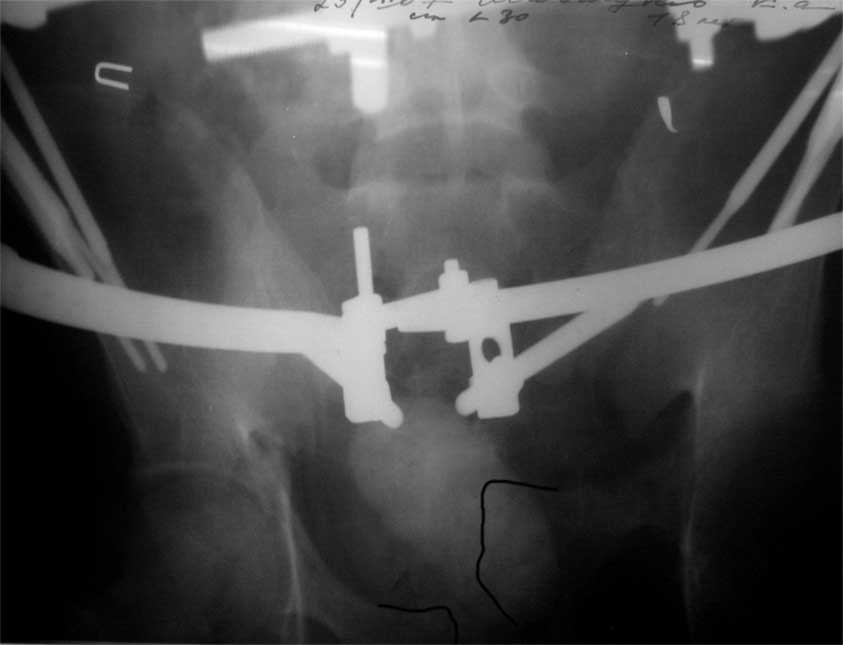

Отправлено Максим Агалаков 06 Июль 2007, 18:52 УНИИТО

Уважаемые коллеги, сложный случай, интересует ваше мнение. Травма 2 месяца назад, в результате ДТП. При поступлении в лечебное учреждение по м/ж выполнено формирование культи на уровне в/3 левого бедра по (травматический дефект левой н/конечности), в послеоперационном периоде раневая инфекция, остеомиелит - экзартикуляция.

Повреждение таза лечилось консервативно. Интересует ваше мнение по поводу тактики лечения, попытаться свести аппаратом, а потом открытый этап (каким доступом/доступами)? другие варианты? С уважением Максим Агалаков